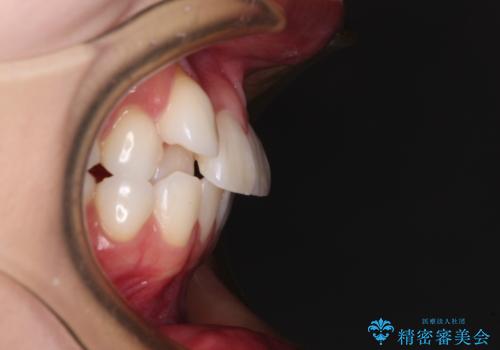

- 八重歯と、それによる正中のズレを気にして来院された患者様です。

口元の突出感は気にしていなかったため、上顎の左右第一小臼歯を抜歯することで、八重歯の解消と上顎の正中を改善していくこととしました。